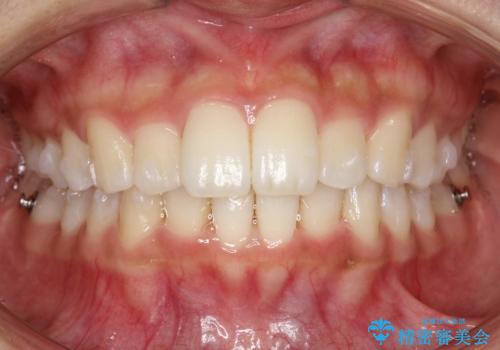

Invisalign インビザラインによる軽度なガタつきの改善

- 奥歯の位置関係はそこまで大きくいじらず、前歯群のみでガタつきの改善を計画しました

奥歯の位置関係に改善の余地はありますが、機能的に問題のない cusp to fossa の関係で咬めているため、前歯のガタつきを前歯のみで改善するというシンプルな計画で、短期間で治療を終了させました。